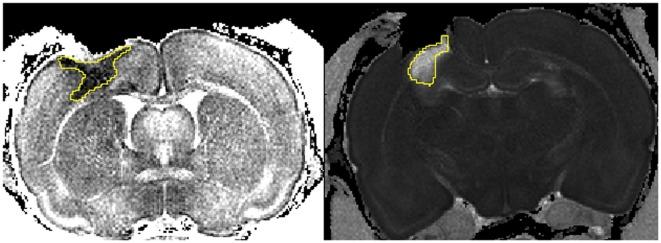

Female Sprague-Dawley rats (n = 73, including sham and naive) were used. The rats were intubated and mechanically ventilated. A controlled cortical impact device created a 3-mm deep lesion in the right parietal hemisphere. Post-injury, rats inhaled either normoxic (22% O2) or hypoxic (11% O2) mixtures for 30 min. The rats were sacrificed at 1, 3, 7, 14, and 28 days post-injury. Serum was collected for S100B measurements using ELISA. Ex vivo magnetic resonance imaging (MRI) was performed to determine lesion size and edema volume. Immunofluorescence was employed to analyze neuronal death, changes in cerebral macrophage- and neutrophil infiltration, microglia proliferation, apoptosis, complement activation (C5b9), IgG extravasation, HIF-1α, and VEGF.

The hypoxic group had significantly increased blood levels of lactate and decreased pO2 (p < 0.0001). On MRI post-traumatic hypoxia resulted in larger lesion areas (p = 0.0173), and NeuN staining revealed greater neuronal loss (p = 0.0253). HIF-1α and VEGF expression was significantly increased in normoxic but not in hypoxic animals (p < 0.05). A trend was seen for serum levels of S100B to be higher in the hypoxic group at 1 day after trauma (p = 0.0868). No differences were observed between the groups in cytotoxic and vascular edema, IgG extravasation, neutrophils and macrophage aggregation, microglia proliferation, or C5b-9 expression.